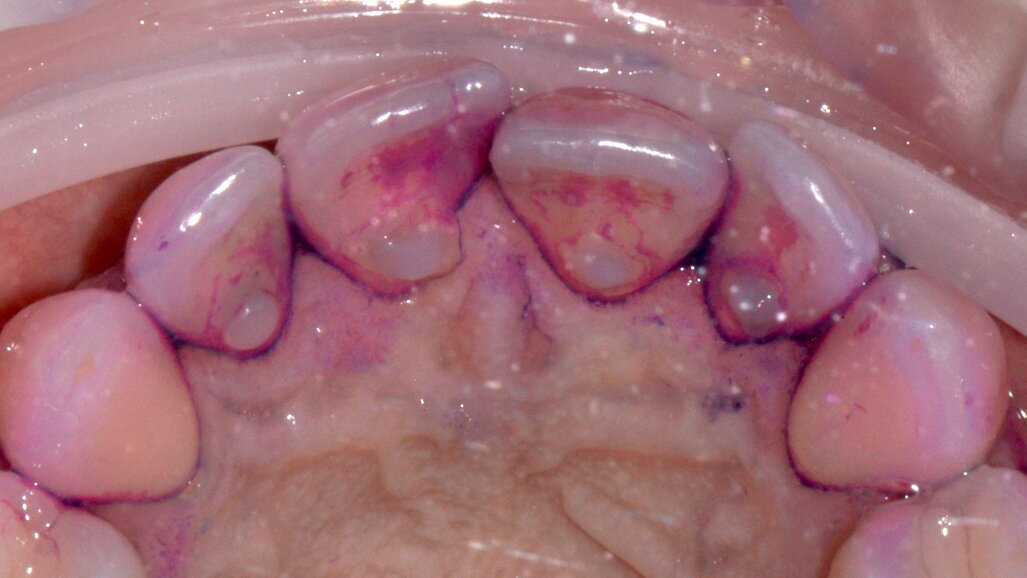

- Applicazione del rilevatore di placca bifasico: permette la distinzione fra i depositi di placca recenti da quelli meno recenti ( 1a-1c);

Figg. 1a-1c - Applicazione del rilevatore di placca che verrà usato come guida durante la terapia, nel versante vestibolare (1a), palatale (1b) e linguale (1c). Si noti lo scarso livello di igiene orale domiciliare e l’assenza di utilizzo dei presidi interdentali.